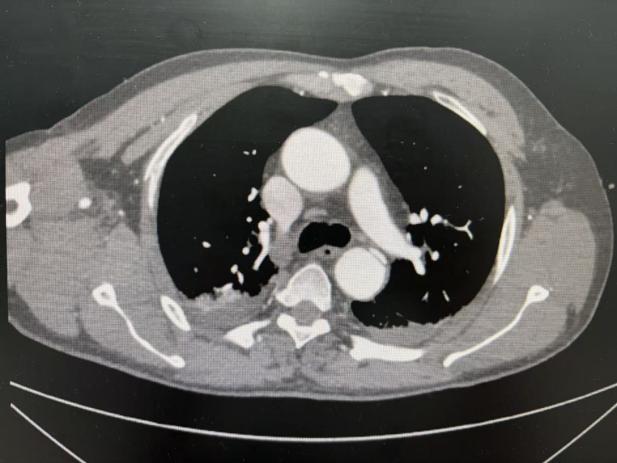

患者因车祸导致严重全身多发伤,ISS评分43分,(ISS评分与死亡率呈正相关,大于16分为严重创伤,大于50分提示存活率极低),创伤性主动脉夹层,右侧股骨干粉碎性骨折,右侧胫腓骨多发骨折,骨盆骨折,右肩关节及右肘关节骨折,肋骨多发骨折,伴有创伤性湿肺、失血性休克、呼吸衰竭等。

急诊中心急诊外科亚专业团队迅速启动创伤中心应急机制,快速评估病情,按照严重创伤“损伤控制复苏原则”,给予气道管理、限制性液体复苏、输血、药物止血、纠正凝血功能障碍、胸带及骨盆带固定等急救措施,为后续救治争取黄金窗口,同时,紧急启动创伤MDT,第一时间召集周围血管科、普外科、胸外科、骨科等科室,仅10分钟创伤团队在急诊抢救室集结完毕,经讨论后一致同意遵循“先救命、后治病”的原则,优先处理严重危及生命的问题,即创伤性主动脉夹层,骨科及胸外科给予支具固定,待患者情况平稳后再行后续手术治疗,汇报科室负责人苗常青主任及外科亚专业许静主任后,立即决定以急诊中心为主导,收住急诊创伤亚重症病房,联合周围血管科秦皓教授团队进行急诊“胸主动脉覆膜支架置入术”,术后患者生命平稳,待一般状态好转后,后续将与骨科协作,共同完成肋骨骨折及肢体骨折手术。